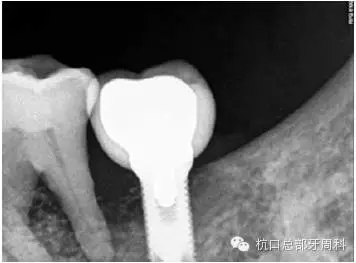

被診斷為種周炎時(shí)全景片  2011

111.webp.jpg